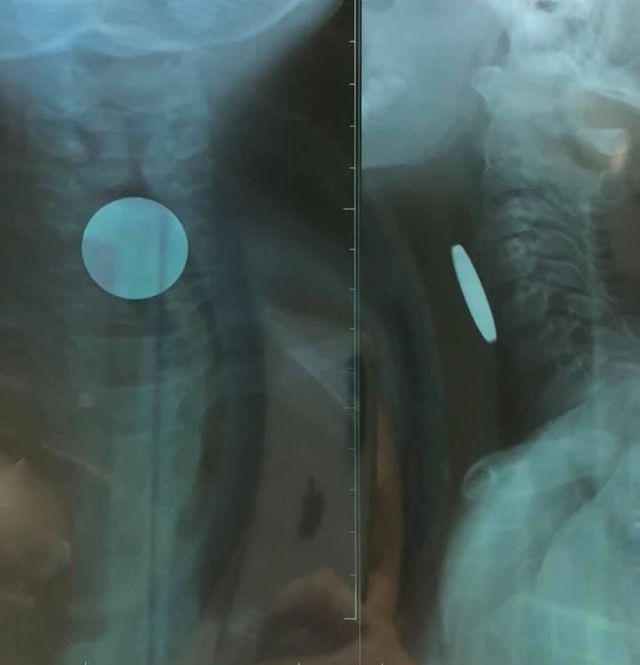

Hình ảnh chụp phim X-quang cho thấy đồng xu kẹt trong thực quản bệnh nhi, gây khó thở, nghẹn, đau tức cổ họng. Bác sĩ đã nội soi gắp đồng xu đường kính 2 cm ra ngoài.